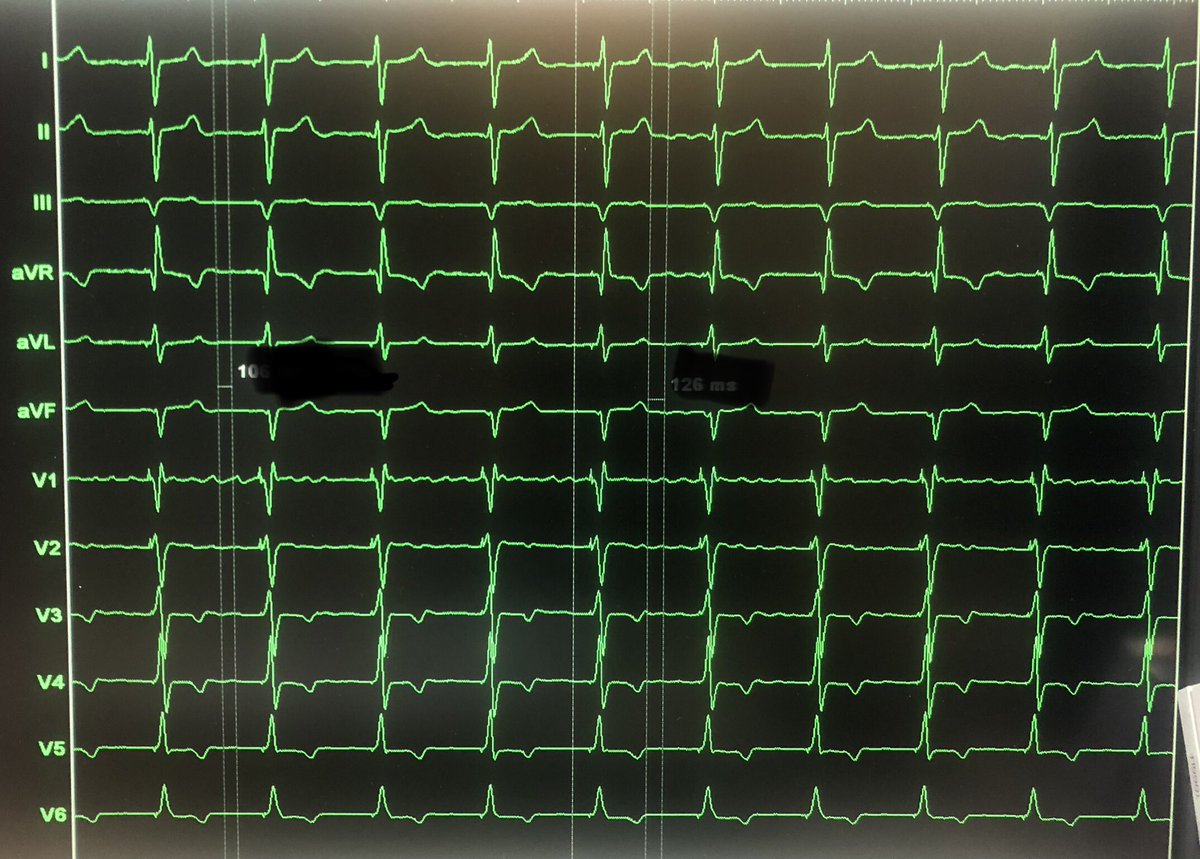

Our first *3* implants in the @AbbottCardio #ASCEND trial yesterday! The lead handles beautifully and we got fantastic LBB capture in all patients. #EPeeps #DontShocktheHis 😂😂